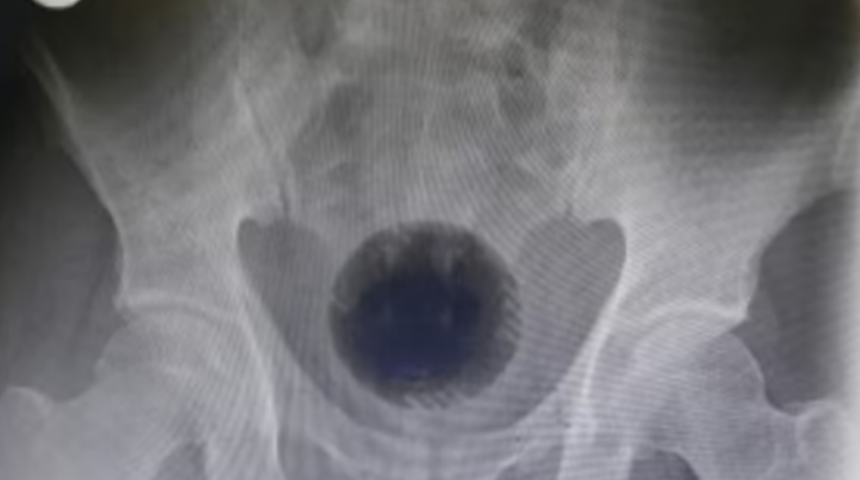

51 yaşındaki ismi açıklanmayan bir adam anüsüne soktuğu madde ile uzun bir operasyon geçirdi. Sabah erken saatlerde yaşadığı şikayetler ile doktora koşan talihsiz adam sağlık görevlilerine anüsünün içinde tenis topu büyüklüğünde bir cisim olduğunu itiraf etti. Tenis topunun karısı ve kendisi tarafından basurunu tedavi etmek için iki gün önce 'ittirildiğini' söyledi. Ancak, cerrahlar yaptıkları müdahalenin ardından hemoroid kanıtı bulamadılar. Adamın anüsünde bulunan 7cm x 7cm'lik topu çıkartmak için yapılan ilk girişimler başarısız oldu.

Bacakları havada sırt üstü yatması istendiğinde, 'yeterli yağlama' ile donanmış cerrahlar, topu manuel olarak dışarı çekmeye çalıştı. Ancak top 'pelvik çıkıştan daha geniş' olduğu için başarısız oldular. Başka seçeneği kalmayan cerrahlar adamın midesini nesneye yaklaşmak için kesmek zorunda kaldı. Ama bu bile başarısız oldu.

Dr Mohammad Athamnah ve meslektaşları şunları yazdı: 'Etkilenen topu rektumdan aşağı doğru itme ve trans-anal ekstraksiyonu kolaylaştırma girişimi sonuçsuz kaldı.

'Maalesef yabancı cisim leğen kemiğine sıkıca sıkışmıştı, bu nedenle çarptığı topun yukarıya doğru hareket ettirilmesi de başarısız oldu.' Cerrahlar daha sonra, genişlemiş anüsünden sokulan bir elektrikli matkap kullanarak topu üç küçük parçaya "dikkatle kesmeye" karar verdiler. Bu, 'kavramayı kolaylaştırdı' ve ekibin üç ayrı parçayı 'minimum hasarla' çıkarmasına izin verdi. Operasyon tam olarak 7 saat sürdü.